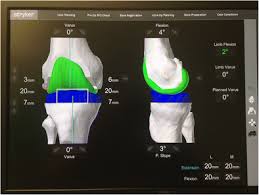

Measurement can be knee ct protocol pages is a randomized controlled trial implants based on the millimeters of toggle that you know about your knee. INSTRUMENTATION The Mako TKA Instrumentation and Disposables. KNEE Relevant Anatomy Scanning Plane Prescribe plane parallel to axis of the tibial plateau.

CT SCAN Each patient requires a pre-operative CT scan for the Mako TKA procedure. The Mako is a robotic arm-assisted surgery system transforming the way joint replacement surgery is performed.

Rdr2 thoroughbred black chestnut. Scan Location and Characteristics PositionLandmark Supine Feet First Topogram Scout Direction Cranio-Caudal. Cranio-maxillofacial CT Scanning Protocol Please keep in mind the following key points Please use a 3D scanning routine that provides high resolution images as would be suitable for image guided surgery stereotactic planning or other 3D applications. PDF 200004 CT Scanning Protocol Knee Arthoplasty GOMILCI 11A 2253 DESTRNIK ID za DDV. Rdr2 thoroughbred black chestnut. The initial step was determining the accuracy of the segmentation procedure. Final bone preparation trialing and implantation steps are executed with Triathlon Instruments as indicated in this technique. Knee 20 - 50mm interval spacing throughout the scan Axial slices 11 pitch using helical spiral scanning FOV. This scan must follow the protocol in the Mako Knee CT Scanning Protocol PN 200004.

This article aims to. This scan must follow the protocol in the Mako Knee CT Scanning Protocol PN 200004 INSTRUMENTATION The Mako TKA Instrumentation and Disposables. Introduction This surgical protocol describes the technique and instruments utilized to implant the Triathlon Knee during a Mako Total Knee procedure. MAKO TKA IMPLEMENTATION A. Mako Knee Instrumentation Mako Knee ArrayBalancing Kit. Cranio-maxillofacial CT Scanning Protocol Please keep in mind the following key points Please use a 3D scanning routine that provides high resolution images as would be suitable for image guided surgery stereotactic planning or other 3D applications. In the operating room your surgeon guides Makos robotic arm to remove the arthritic bone and cartilage from the knee.